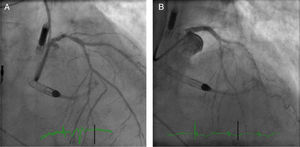

An electrocardiogram obtained immediately upon admission showed stable right ventricular pacing rhythm. TTE showed a severely depressed LVEF (34%) with global hypokinesis of the left ventricle. There was no evidence of intracavitary thrombi. Coronary angiogram revealed 70% stenosis of the distal left main coronary artery (LMCA) (Medina Classification 1,0,1) and chronic total occlusions of the proximal LCX and middle RCA, both partially perfused by collateral vessels (Figure 2A). The patient was rejected for CABG because of high operative risk and poor distal grafting targets. After a Heart Team discussion, it was decided to proceed with a PCI of the distal LMCA to the LAD with the support of a 4-l/min Impella CP®.

The ostium of the LMCA was catheterized using a 6-Fr Extra Back-Up 3.5 guiding catheter (Cardinal Health) via right radial artery. A Whisper (Abbott Vascular) guidewire was advanced into the LAD and multiple pre-dilation inflations were performed using a 2.5×8-mm Quantum™ Maverick™ balloon and a 3×8-mm TREK balloon. Then a 3.5×18-mm Onyx™ (Medtronic) stent was successfully deployed in the distal LMCA towards the proximal LAD. The stent was subsequently post-dilated with a 4.0×15-mm Quantum™ Maverick™ balloon at 20 atm, with a good final angiographic result (Figure 2B). The patient remained hemodynamically stable throughout. The Impella CP® assist device was withdrawn and the sheath was removed at the end of the procedure. The right femoral artery access site was closed using a ProGlide device.